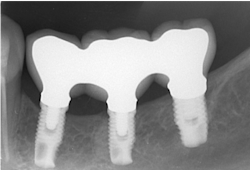

The same arguments have been advanced for not splinting adjacent implants in segmental reconstructions (figure 1). Plaque-related peri-implantitis is the most common biological complication in implant dentistry. A passive fit of prostheses on their supporting implants is considered essential for minimizing mechanical and biological overloading. On the other hand, it is also claimed that splinting can prevent overloading (figure 2). Screw loosening and fracture of veneering material are the most common mechanical complications of loading, although there is little evidence that it results in loss of integration.

Figure 1: Nonsplinted adjacent implants